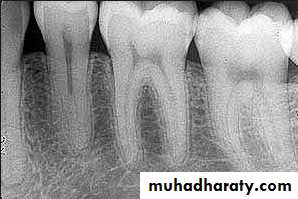

Evaluation of radiographic survey

All prospective abutment teeth must be critically evaluated4/2/2018

Root size, length and form

Teeth with large or long roots - Greater periodontal supportTapered or conical roots- un favorable

Multi rooted teeth with divergent roots are stronger abutment teeth than single rooted, multi rooted teeth with fused roots.4/2/2018

Signs of positive bone factor

A supportive trabecular patternHeavy cortical layer

Dense lamina dura

Normal bone height

Normal periodontal ligament space.

If retrograde bone changes occur, the patient has a negative bone factor ; prognosis is poor.